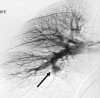

Hughes-Stovin Syndrome (HSS) is a very rare clinical disorder characterized by thrombophlebitis and multiple pulmonary and/or bronchial aneurysms. Less than 40 published cases of HSS have been described in English medical literature so far. The exact etiology and pathogenesis of HSS is unknown; possible causes include infections and angiodysplasia. HSS has also been considered as a variant of Behcet's disease (BD). Patients with HSS usually present with cough, dyspnea, fever, chest pain and haemoptysis. The management of HSS can either be medical or surgical. Medical management includes the use of steroids and cytotoxic agents. Cyclophosphamide, in particular, is a favored therapeutic agent in this regard. Antibiotics have no proven role in HSS while anticoagulants and thombolytic agents are generally contraindicated due to an increased risk of fatal hemorrhage. However, their use may be considered with great care under special circumstances, for instance, intracardiac thrombi or massive pulmonary embolism. For cases of massive hemoptysis due to large pulmonary aneurysms or those with lesions confined to one segment or one lung, lobectomy or pneumectomy can be carried out. However, surgical risks merit serious consideration and must be discussed with the patient. Transcatheter arterial embolization has emerged as a less invasive alternative to surgery in selected cases of HSS. Overall, patients with HSS have a poor prognosis and aneurysmal rupture is the leading cause of death. However, early diagnosis and timely intervention is crucial in improving the prognosis. There is a need to clearly elucidate the genetic, etiologic and pathologic basis for HSS in the future. Although most of the evidence put forward to refute the role of an infectious agent in the etiology and pathogenesis of HSS is based on negative blood and other body fluid cultures, more robust objective assessment is needed through the use of electron microscopy or 16 sRNA studies. The development of better therapeutic agents is also needed to address and prevent the serious consequences arising from pulmonary arterial aneurysms seen in BD and HSS. Also, the issue of anticoagulation in these patients is challenging and requires further deliberation.